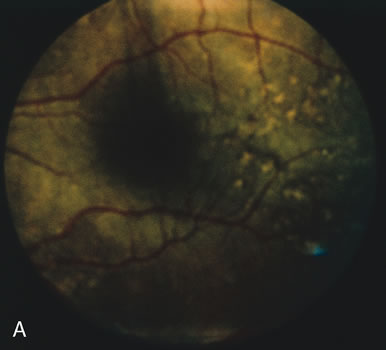

In retinitis pigmentosa (RP), the pigment abnormalities of atrophy, migration, and clumping are made apparent by transmitted hyperfluorescence and blocked hypofluorescence (Fig. 1A). Patients who have very minimal pigmentary alterations (pauci pigmentary RP) or no pigment abnormalities (RP sine pigmento) may show the abnormalities on fluorescien angiography (FA). It is uncommon to see choriocapillaris atrophy except in the late stages. This finding corresponds to the histopathology, which shows that the earliest abnormalities are in the photoreceptors and that the choroid is normal.1